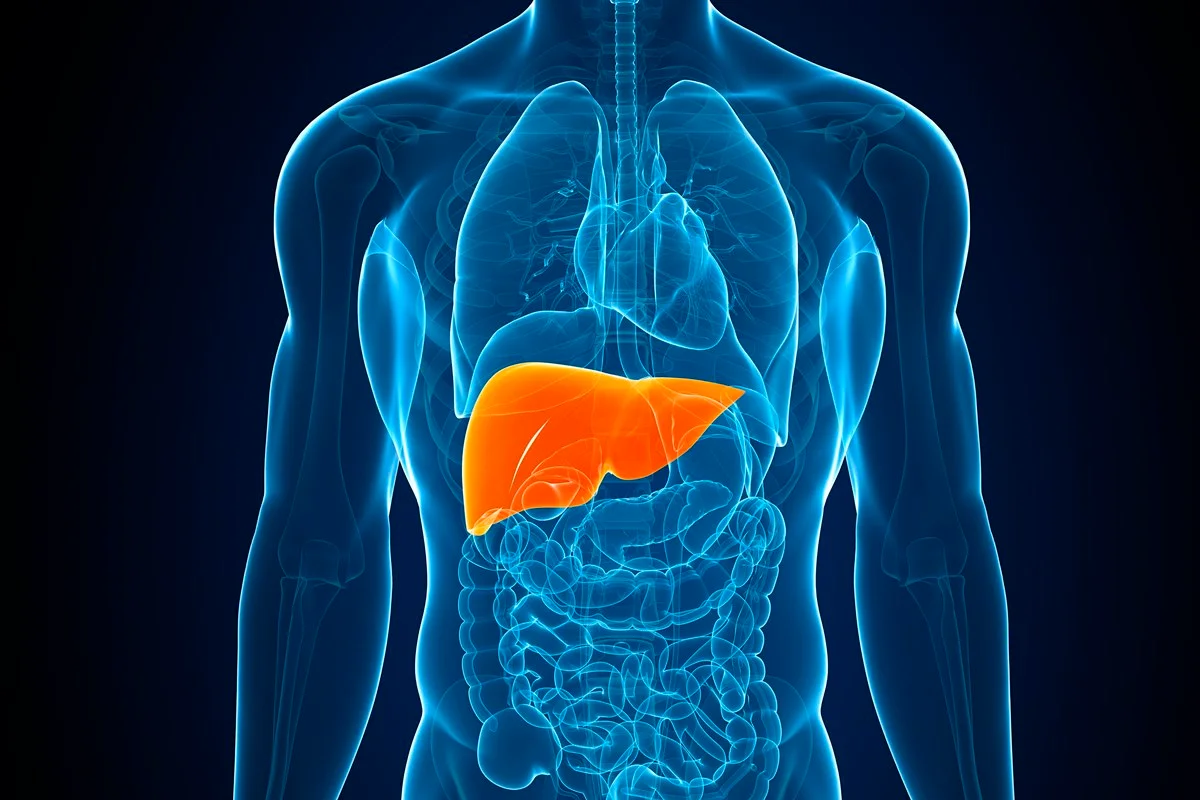

A esteatose hepática é popularmente conhecida como gordura no fígado

A condição de gordura no fígado acomete 30% da população mundial, segundo o artigo